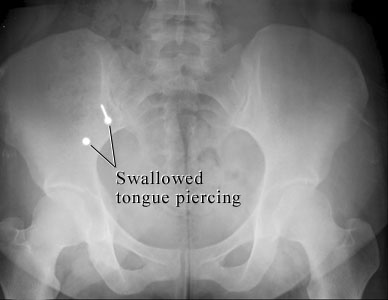

Courtesy of Intermountain Medical Imaging, Boise, Idaho.

This X-ray of the belly shows two metal parts inside the bowel that were swallowed from a tongue piercing. The sharp stud could cause problems, while the blunt part is not likely to cause problems. Both parts are likely to pass in the stool.